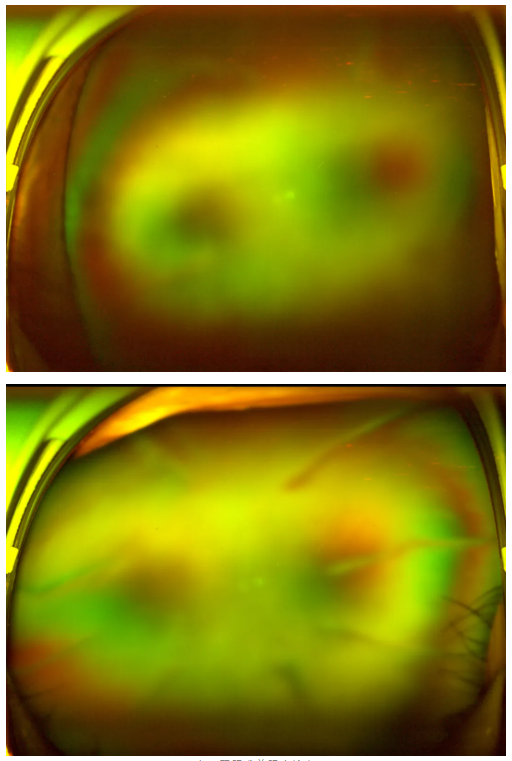

老王雙眼術(shù)前眼底檢查

“別灰心,好好配合治療,你還是有很大機(jī)會能恢復(fù)部分視力的。”王曉波主任的話像一顆定心丸,讓老王懸著的心得以放松。在醫(yī)生的指導(dǎo)下,老王先積極穩(wěn)定血糖,為后續(xù)治療打下堅(jiān)實(shí)基礎(chǔ),隨后多次轉(zhuǎn)機(jī)重返廈門眼科中心辦理入院,準(zhǔn)備接受針對性治療。